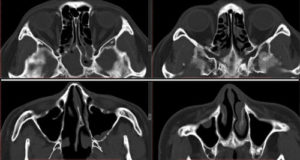

Для диагностики сфеноидита необходимо выполнение Компьютерной томографии (КТ) пазух носа.

Нередко, особенно при хроническом течении, врачи прибегают к проведению компьютерной томографии. С ее помощью удается послойно оценить строение носа и придаточных его пазух. Главное преимущество этого метода – это возможность определить размер соустий, который влияет на частоту рецидивов заболевания и отражается на тактике лечения.

Единственными методами, которые наверняка могут определить сфеноидит, являются компьютерная томография (КТ) или магнитно-резонансная томография (МРТ) –